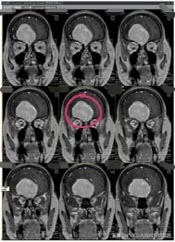

近段时间来,林阿姨头痛越来越重,偶尔还会出现小便失禁,林阿姨这才有所警觉。在医院头颅CT检查,显示:前颅底巨大占位,考虑脑膜瘤可能性大。林阿姨吓坏了,半辈子都平平安安,想不到脑子里居然有这么大的一个肿瘤。

孩子们也非常担忧,通过四处打听,林阿姨来到了广东三九脑科医院。进一步影像检查也提示是:前颅窝底巨大占位性病变,考虑脑膜瘤可能性大。

肿瘤体积巨大,占位明显,医院副院长、神经外五科主任鲁明和团队一起经过讨论,快速制定了安全且风险较小的手术方案,术中需要避开重要血管,尽最大可能全切除肿瘤。术前进行全脑血管造影,影像显示:前颅底异常染色,呈类圆形,肿瘤主要是由右侧脑膜中动脉前支、右侧眼动脉分支参与供血;决定先行肿瘤栓塞术,术后加压包扎送病人至手术室,行“前颅底巨大脑膜瘤切除术”。肿瘤周围血管丰富,已侵犯重要神经;导航准确定位,显微镜下见肿瘤起源于大脑镰及前颅底,阻断肿瘤血供后,先钨刀切除左侧额部部分肿瘤,再超吸切进行瘤内减压,最终镜下将肿瘤切除干净。